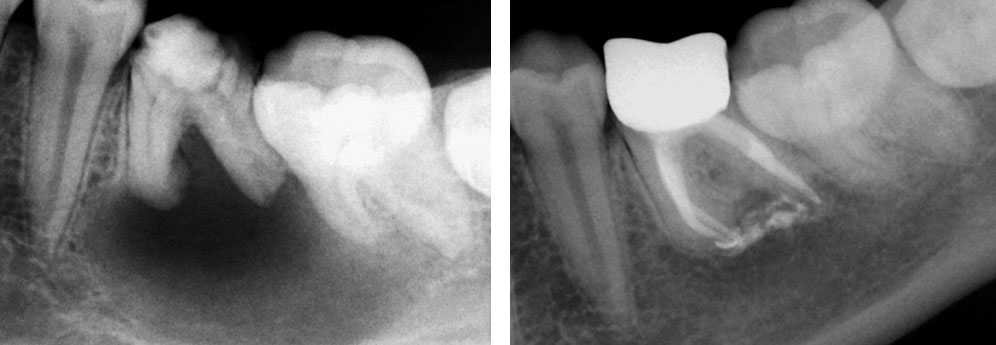

Age of patient: 15 years

Tooth: left mandibular first molar. Poor restorative prognosis. Very large lesion.

Work done: Obturation done after multiple calcium hydroxide dressings over 5 months and seeing lesion decrease in size. Fiber-post placed in distal canal. Core build-up done with Luxacore composite. Adv crown.

Notes: This is endo done for a “holding period” for implants later on. Healing of bone ensures a more favorable environment for implant placement.

Pre-op

Obturation done after 5 months of calcium hydroxide

May 2015 – 3 year recall

Pre-op & 3 year recall